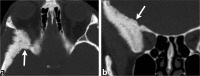

Calvarial lesions are often asymptomatic and are usually discovered incidentally during computed tomography or magnetic resonance imaging of the brain. Calvarial lesions can be benign or malignant. Although the majority of skull lesions are benign, it is important to be familiar with their imaging characteristics and to recognise those with malignant features where more aggressive management is needed. Clinical information such as the age of the patient, as well as the patient's history is fundamental in making the correct diagnosis. In this article, we will review the imaging features of both common and uncommon calvarial lesions, as well as mimics of these lesions found in clinical practice. TEACHING POINTS: • Skull lesions are usually discovered incidentally; they can be benign or malignant. • Metastases are the most frequent cause of skull lesions. • Metastatic lesions are most commonly due to breast cancer in adults and neuroblastoma in children. • Multiple myeloma presents as the classic "punched out" lytic lesions on radiographs. • Eosinophilic granuloma is an osteolytic lesion with bevelled edges.